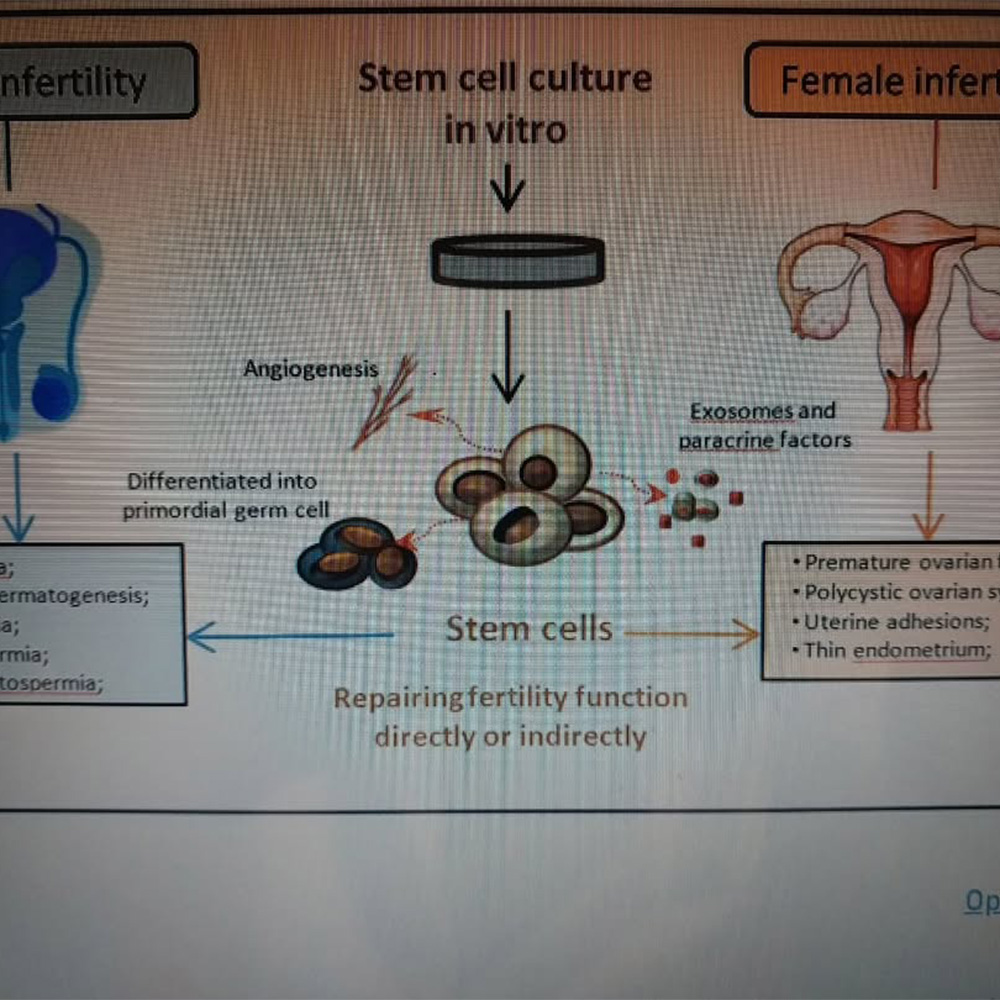

Kısırlık Çözümü

Kök Hücre

Gelişmiş tıbbi çözümler sunarak sağlığınızı destekliyoruz. Kök hücre ve PRP tedavileri, obezite cerrahisi, metabolik cerrahi ve bireysel sağlık danışmanlığı hizmetlerimizle yanınızdayız.